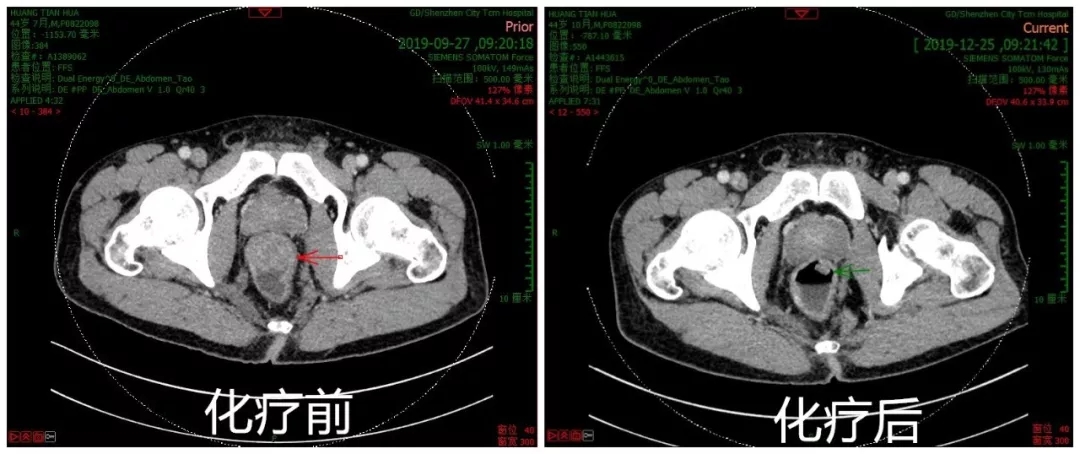

化疗后盆腔CT图像肿瘤明显缩小

化疗后盆腔CT图像 肿瘤明显缩小